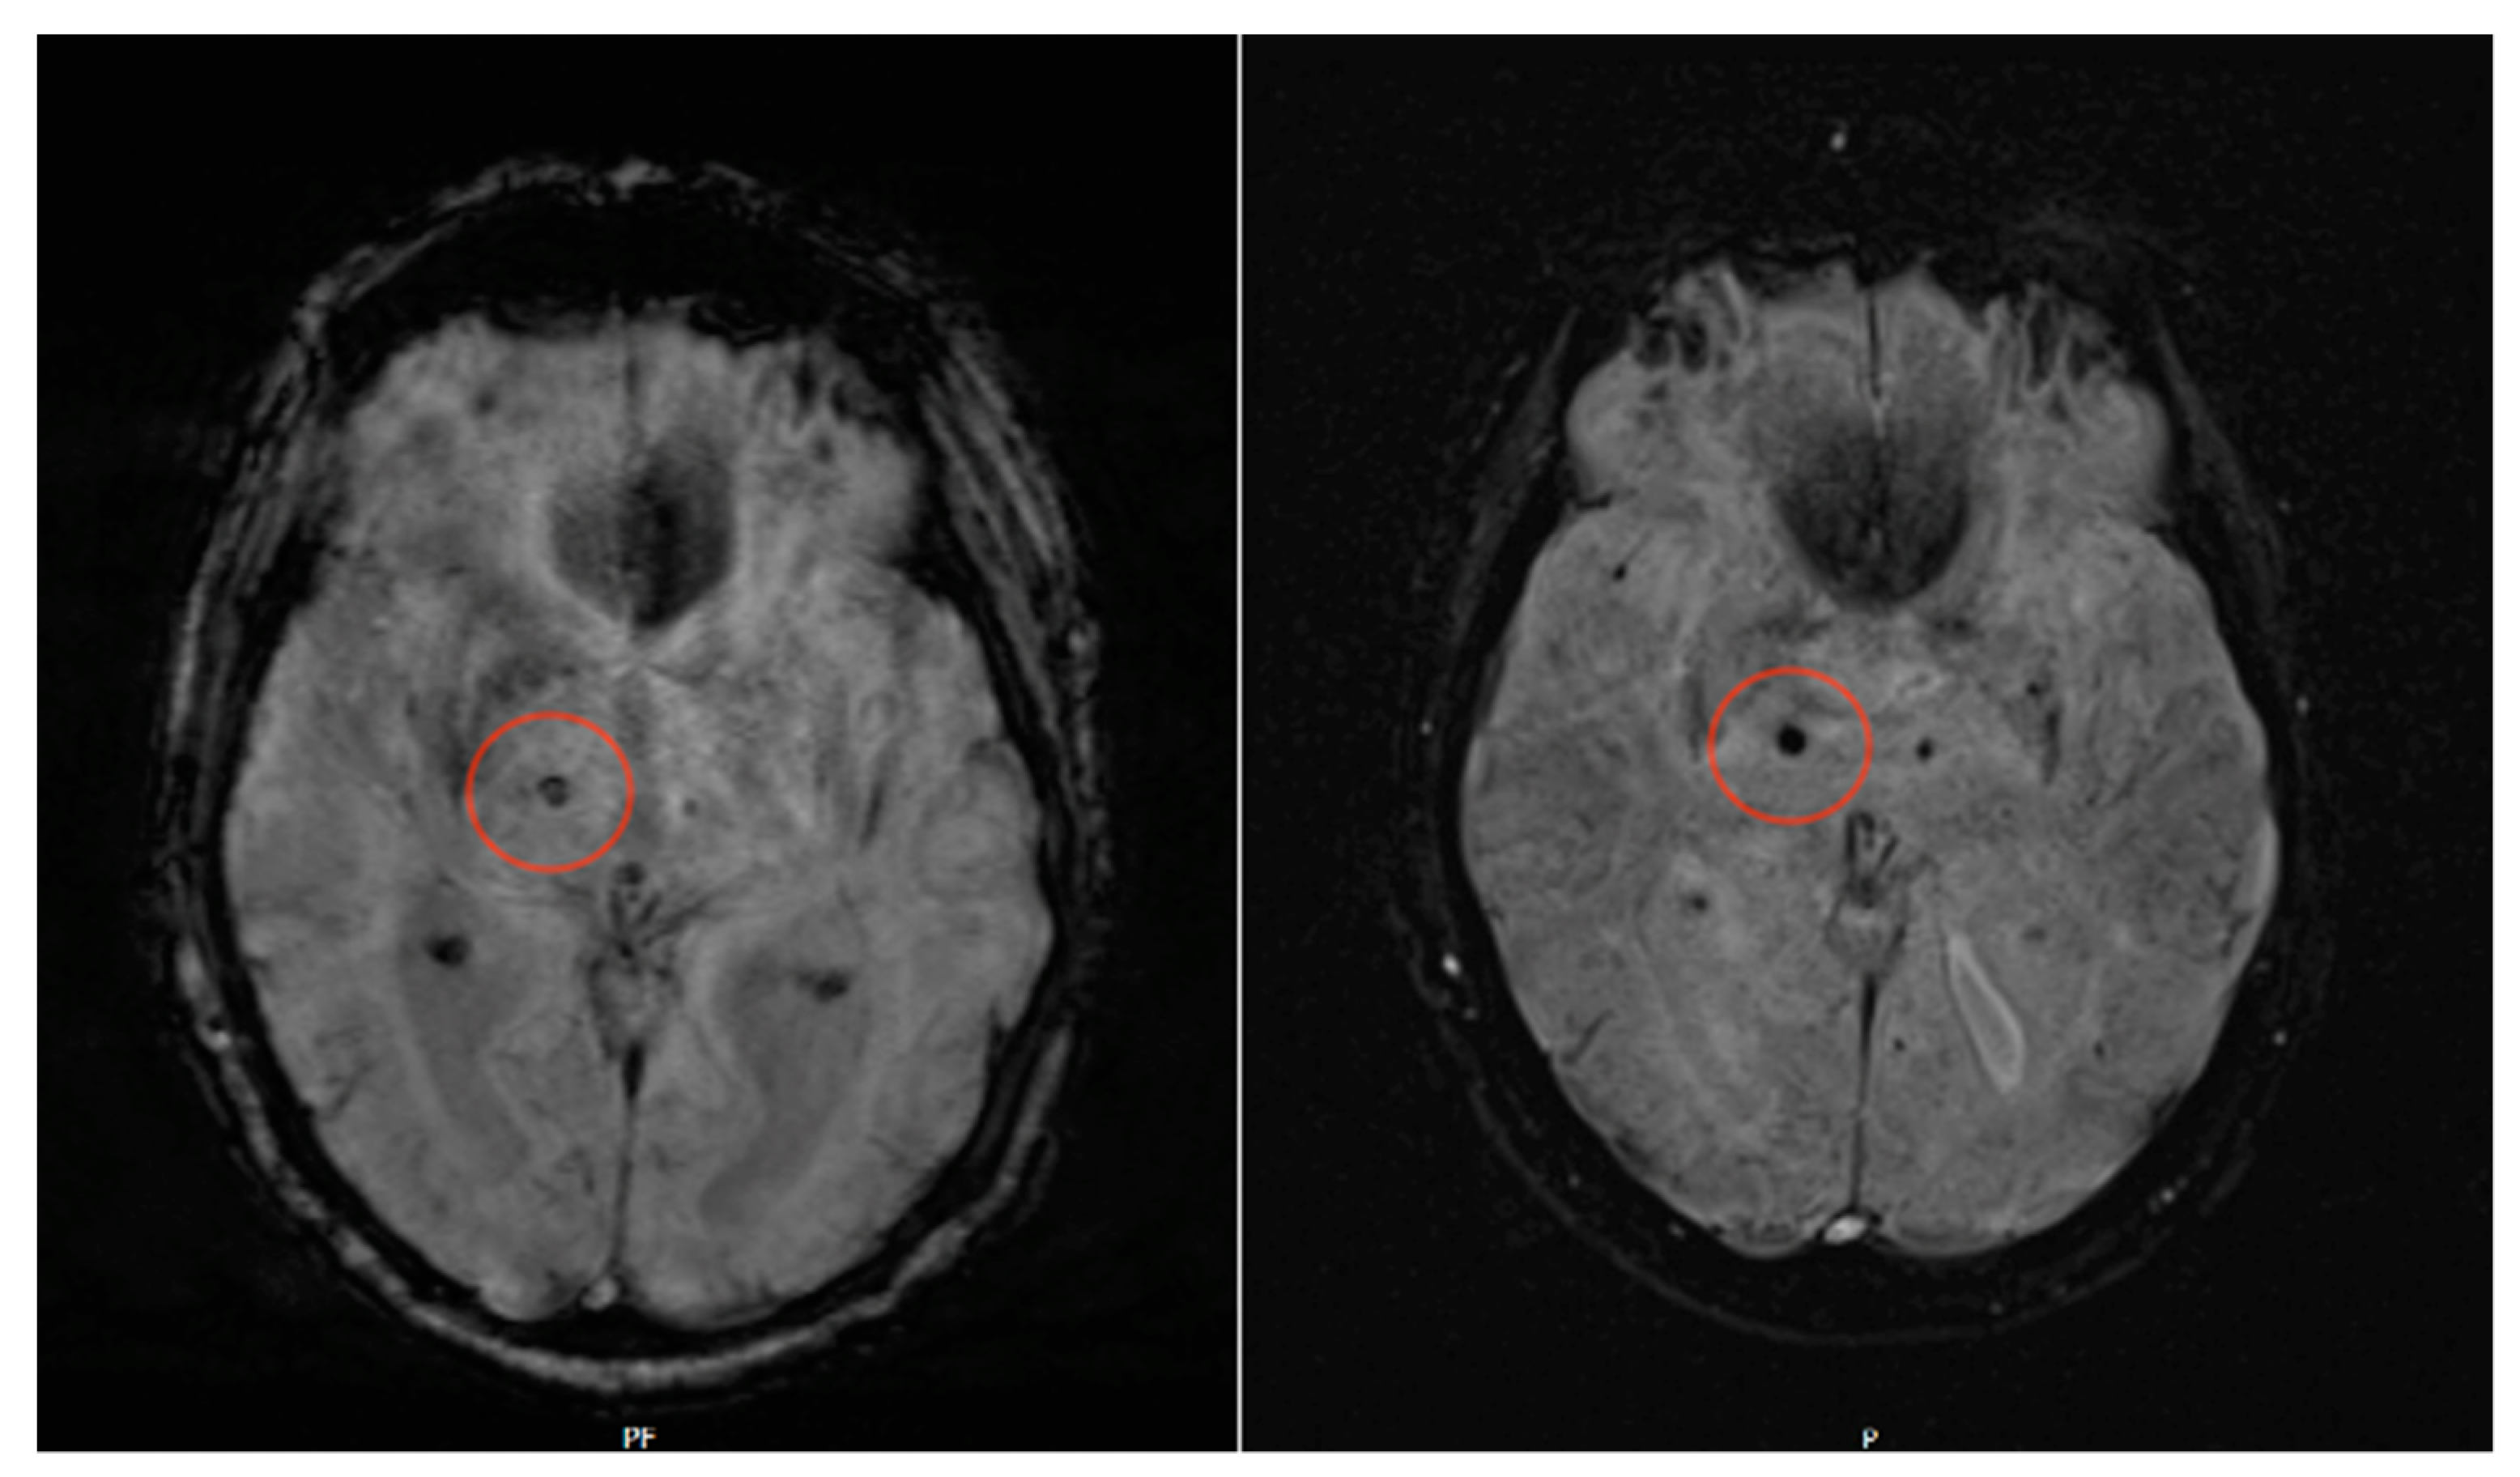

Prospective Assessment of Cerebral Microbleeds with Low-Field Magnetic Resonance Imaging (0.55 Tesla MRI)

| Patient 21 | 86 | Yes | >10 | Bilateral Thalamus | 25 |